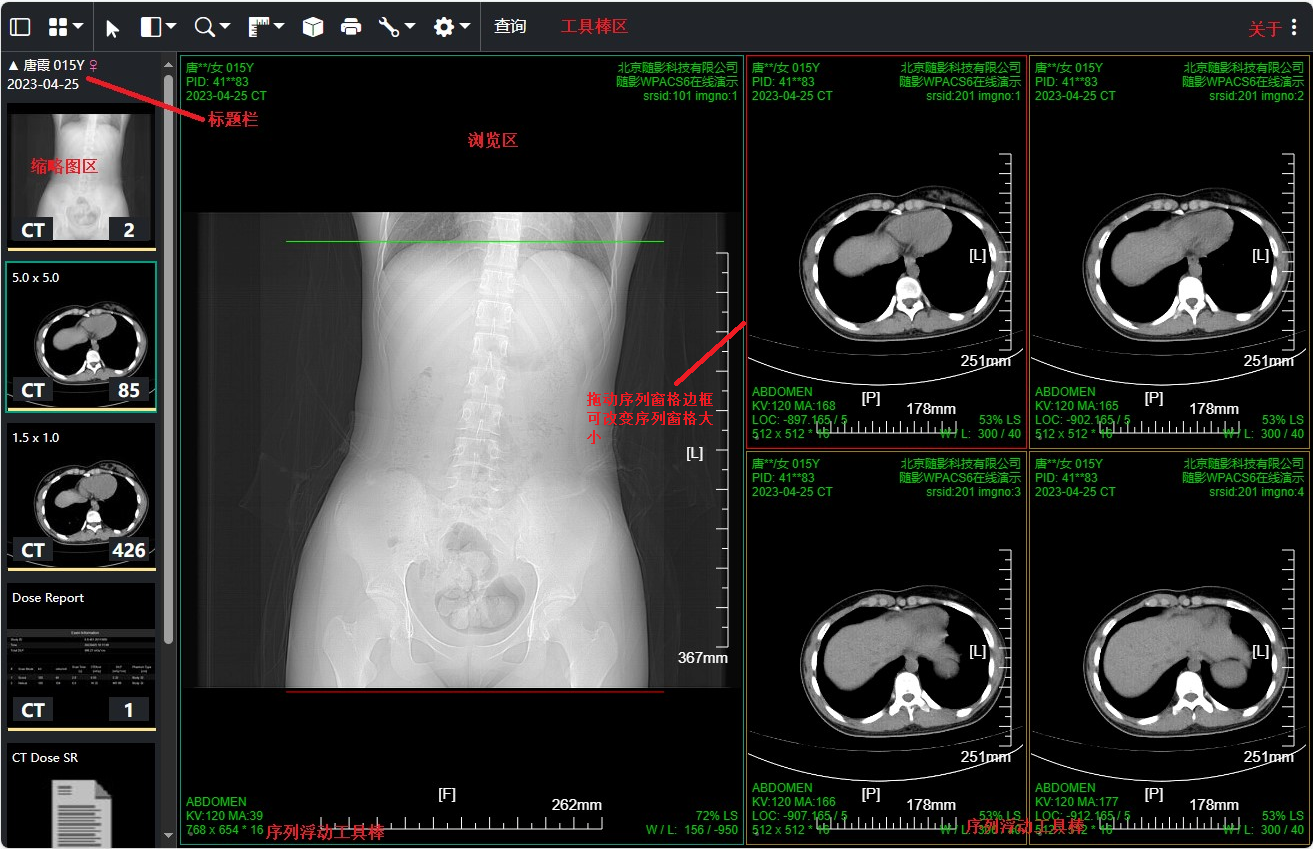

工具棒区域按钮菜单可任意配置,同时支持不同的图像类型或不同屏幕大小配置不同的按钮菜单布局

点击缩略图标题栏 折叠/展开 当前检查缩略图;点击 "关于" 按钮查看当前wpacs当前版本以及浏览器信息,改变工具棒停靠位置

多序列窗口布局时拖动序列窗格边框可改变窗格cell的大小

鼠标移动到序列浏览区下方 显隐序列浮动工具棒(工具棒上按钮用户可自定义配置);

触摸屏点击序列浏览区左下角可弹出序列浮动工具棒并固定;

序列浮动工具棒可播放序列或当前多帧图像,改变播放速率; 多序列布局时可在1x1序列布局和当前序列布局之间切换;